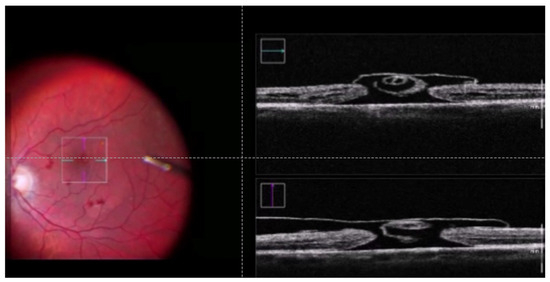

Figure 1

Clinical Outcomes of Full-Thickness Macular Holes with Epiretinal Proliferation Without Posterior Vitreous Detachment

by Kota Kakehashi, Reio Sekine, Tatsuya Jujo, Naoto Uchiyama, Akiko Endo, Naoto Tokuda and Yasushi Kitaoka

Background and Objective: To elucidate the clinical characteristics of full-thickness macular holes (FTMHs) with epiretinal proliferation (EP) without posterior vitreous detachment (PVD). Material and Methods: A retrospective and exploratory study reviewed clinical records of patients with FTMHs with EP without PVD [...] Read more.

Background and Objective: To elucidate the clinical characteristics of full-thickness macular holes (FTMHs) with epiretinal proliferation (EP) without posterior vitreous detachment (PVD). Material and Methods: A retrospective and exploratory study reviewed clinical records of patients with FTMHs with EP without PVD (5 eyes: EP group) and FTMHs without EP without PVD (32 eyes: non-EP group). Swept-source OCT images were analyzed for macular structure. Statistical comparisons were made between clinical characteristics and surgical outcomes. Results: The EP group had two eyes with non-closure of macular holes (40%) (p = 0.01) and three eyes with ellipsoid zone defects (60%) (p = 0.01 compared with the non-EP group). Conclusions: Although limited by a small sample size, this pilot study suggests that the observed trends—such as a lower closure rate and more outer retinal disruption in the EP group—may indicate differences in pathogenesis and surgical outcomes compared to the non-EP group. However, these findings should be interpreted with caution due to statistical limitations. Further prospective studies with larger cohorts are needed to validate these preliminary findings and better understand the underlying pathogenesis. Full article